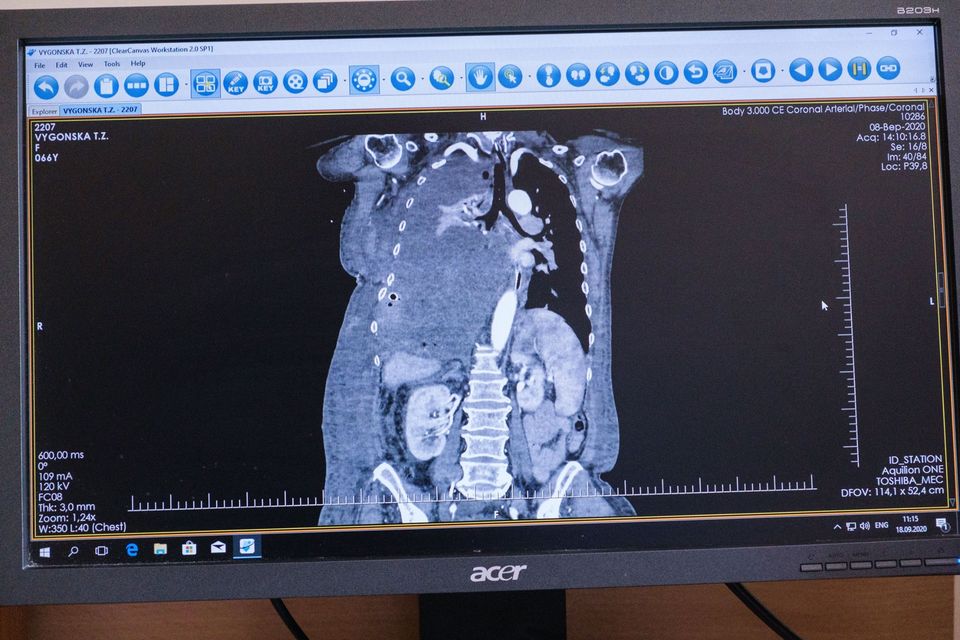

"В мае Татьяна Выгонская почувствовала сильную одышку и слабость, поэтому была вынуждена обратиться за медицинской помощью по месту жительства, а оттуда ее отправили в Хмельницкую областную клиническую больницу, где провели обследование и взяли ряд анализов. Диагноз - солитарная фиброзная опухоль правого гемиторакса. Новообразование было таким большим, что срослось, зажало правое легкое и давило на левое легкое и сердце. Из-за размера опухоли женщину отказались оперировать, а местный онколог посоветовал проконсультироваться у хирурга Виталия Соколова в Киеве", - говорится в тексте сообщения.

"Сложность операции заключается в том, что, во-первых, тяжелое соматическое общее состояние пациентки – локализация опухоли непростая, есть опасность большой кровопотери, повреждения легких и остановки сердца. Во-вторых, технически сложно. Должны быть собраны соответствующие специалисты и необходимое оборудование", – пояснил главный врач "Феофании" Игорь Семенив.

В "Феофании" медики провели операцию по удалению 4,5-килограмовой опухоли. Фото: facebook.com/president.gov.ua